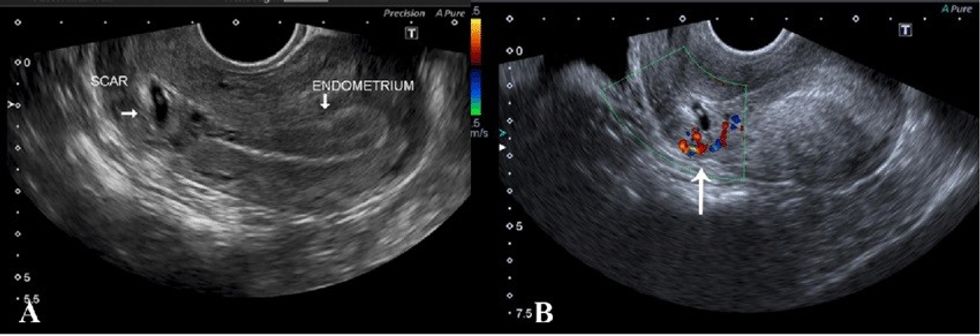

Diagnostikimi bëhet lehtësisht përmes ekzaminimit gjinekologjik dhe ekzaminimit me ultrazë.